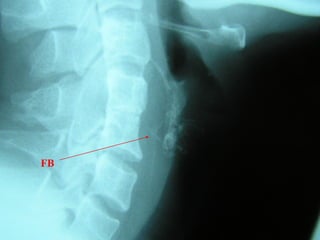

FB - Throat

History

Localised

Below post-cricoid region - midline

Mouth/ oropharynx – localised to side

Time of ingestion

High risk

Sensory deprivation eg dentures (adults )

Otalgia, neck tenderness, fever, chest or back pain,

haemetamesis

Examination

Distress

Unable to swallow saliva

Tracheal rock positive

Swallow test positive

FB Throat - Investigations

Lateral neck XR

CXR

Barium swallow

CT scan – without contrast

Rigid oesophagoscopy

FB

Hyoid bone

Thyroid cartilage

Cricoid cartilage

Osteophyte

FB Throat

>50% of ingested FB cannot be found!

Discharge with symptomatic treatment

Cover with antibiotics if diabetic patient or

immunocompromised

FB advice

Chest pain, fever, increasing symptoms